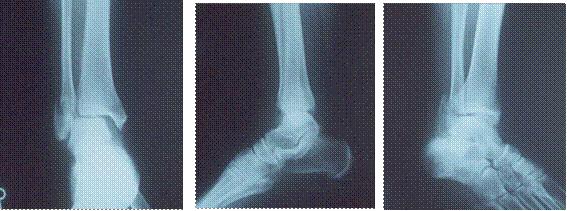

X線所見:正面像において、腓骨遠位端部の骨折及び、遠位骨片の外側への転位が認められた。側面・斜位像において、末梢骨片の後上方への転位が認められた。加えて距骨の外方への変位が認められた(図1)。

図1 初診時における受傷部のレントゲン写真

左 正面像 腓骨遠位端部に骨折線が認められ、遠位骨片が外下方に転位している

中 側面像 距骨と脛骨の解剖学転位はほとんどみられない。

右 斜位像 近位骨片の前内方への転位が認められ、遠位骨片が後下方に転位している。